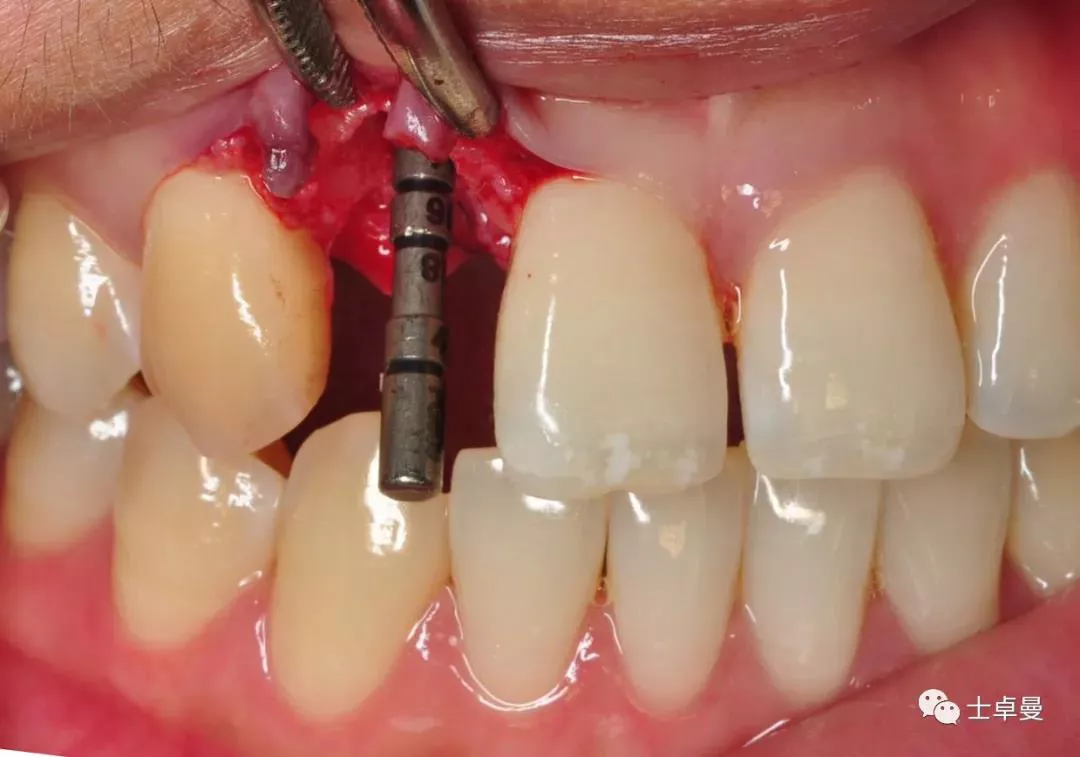

·       腭侧壁上定点,先锋钻确认种植体植入位置;

偏腭侧定点

·       放置指示杆确定种植体方向,方向无误后,逐级备洞,腭侧骨板部门攻丝,植入3.3mm×14mm士卓曼钛锆合金亲水表面骨水平锥柱状种植体 (BLT) 种植体;

方向杆显示种植体轴向位置

·       初期稳定性大于35NCM,ISQ值73;